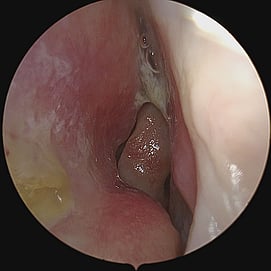

Turbinate Reduction

Turbinate reduction for obstructive sleep apnea is a surgical procedure aimed at improving nasal airflow and reducing upper airway resistance during sleep, thereby potentially alleviating symptoms of OSA. The turbinates are structures inside the nose that help humidify and filter air as it passes through. In the case of turbinate enlargement (hypertrophy), they can contribute to nasal congestion and obstruction, which may exacerbate or contribute to sleep-disordered breathing.